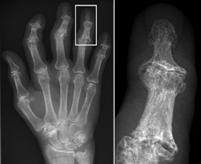

Description English:

X-ray of right fourth proximal

interphalangeal (PIP) joint with bone erosions by rheumatoid arthritis. Taken October 2002. Same joint is partially healed on a follow-up X-ray

after treatment with conventional disease-modifying

antirheumatic drugs(DMARDs) one year later: File:X-ray of right fourth PIP joint with partially healed bone erosions by

rheumatoid arthritis.jpg